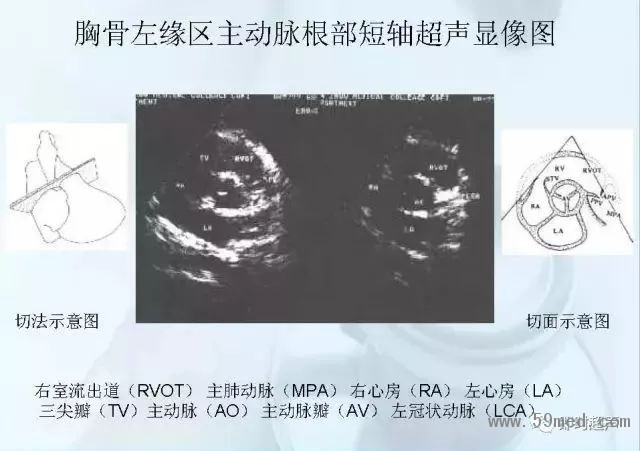

新聞中心 收藏!正常B超解剖圖譜,超實用!